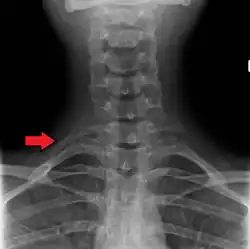

Variation

Variations in the number of ribs occur. About 1 in 200–500 people have an additional cervical rib, and there is a female predominance.[13] Intrathoracic supernumerary ribs are extremely rare.[14] The rib remnant of the 7th cervical vertebra on one or both sides is occasionally replaced by a free extra rib called a cervical rib, which can mechanically interfere with the nerves (brachial plexus) going to the arm.